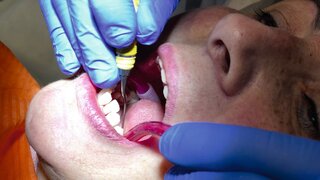

Gemeinschaftstagung der Fachgesellschaften in MünchenZahnerhaltung! Zahnerhaltung! Zahnerhaltung! Über 700 Zahnärztinnen und Zahnärzte reisten Ende November in die bayerische Landeshauptstadt, um sich über neue Forschungsergebnisse und moderne Therapien für eine langfristige Zahnerhaltung zu informieren. 28.11.2023 Zahnmedizin